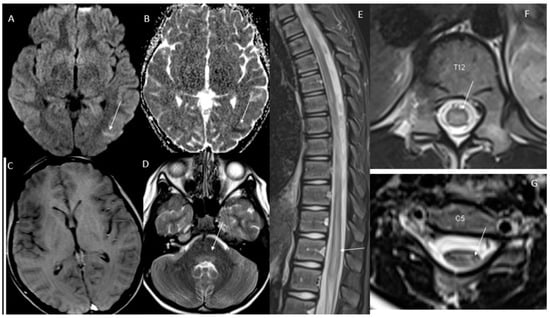

6.2. Neuroimaging Findings and Pathways Affected Leading to Urinary Retention